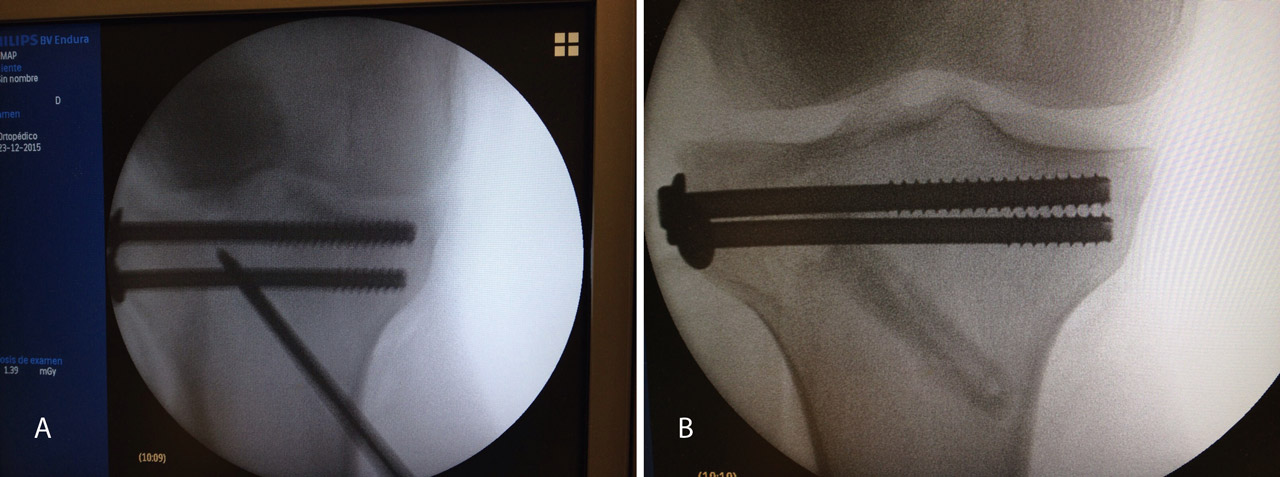

A raíz del artículo de Caspari(11), comenzamos a utilizar la artroscopia en nuestro medio en las fracturas de meseta tibial Schatzker de tipo II, en las que realizábamos la elevación del fragmento hundido mediante el uso de impactores desde la zona diafisometafisaria de la tibia, relleno del defecto con cemento biocompatible y fijación con tornillos canulados con arandela. Publicamos nuestra experiencia en los Cuadernos de Artroscopia en 1998(12)(Figuras 2 y 3).

Figura 3. Técnica quirúrgica en fracturas de meseta tibial asistidas por artroscopia: relleno con cemento biocompatible y fijación con tornillos canulados de esponjosa.

Posteriormente, realizamos un orificio en la cortical de la diáfisis de la tibia a cierta distancia del foco de fractura mediante una broca canulada de 8 mm que nos permita introducir un impactor curvo con el que percutir en el fragmento hundido hasta colocarlo a nivel de la superficie articular, controlando la reducción por artroscopia y radioscopia de manera simultánea.

Una vez reducida la fractura, fijamos los fragmentos de manera provisional con una o más agujas de Kirschner y las vamos sustituyendo por tornillos canulados de 4,5 mm. Cuando realizamos este procedimiento, ampliamos habitualmente un centímetro la herida de introducción del tornillo para poder colocar un pequeño separador que nos permita rechazar los elementos neurovasculares y tendinosos de la zona del tobillo.

Figura 10. Colocación de los tornillos. Control radioscópico.

Figura 11. Control radiológico anteroposterior y lateral.